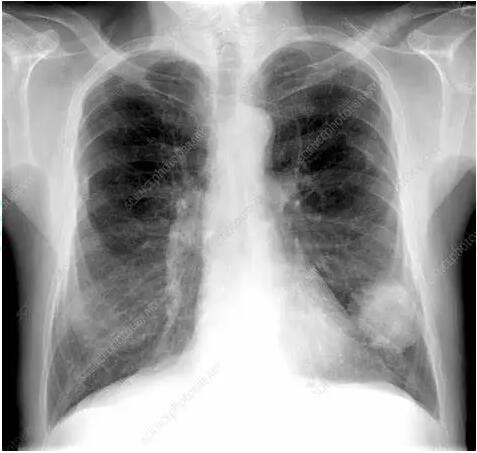

No.1 X线胸片

胸片体检和筛查的常规方法,其经济实惠,是筛查肺癌的重要基础手段。恶性肿瘤在胸片上可出现特殊的X 线征象,如分叶征、毛刺征、血管集束征等。而在肺癌早期还未长成肿块时,常不易与炎症相鉴别。医生会根据患者症状决定是否进行抗炎治疗后复查。若肿块不变小,反而增大,就应高度怀疑肺癌。

由于胸片是胸部器官、组织的叠加投影,胸片精细显示不足,对于一些1cm左右的早期肺癌常不能显示。